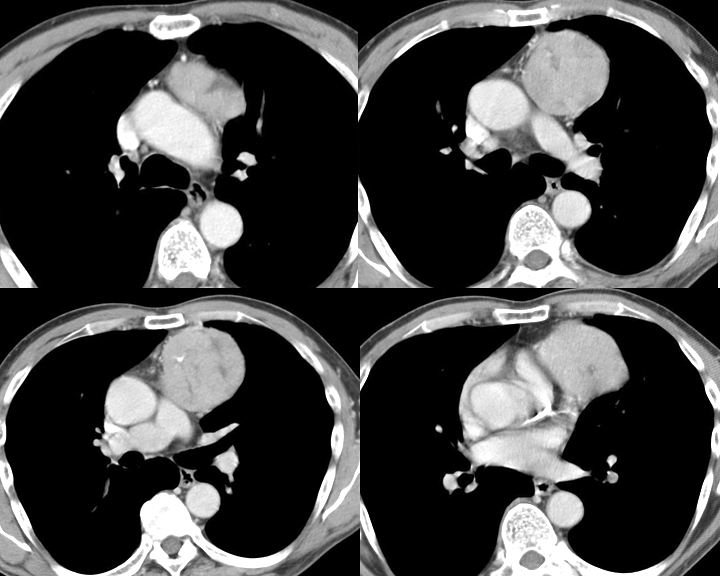

Thymoma